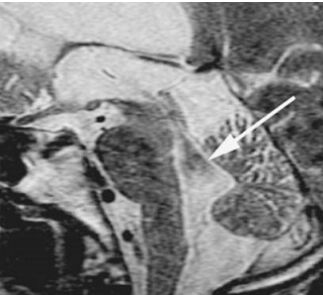

32.中年男性創傷,矢狀面重組的(sagittal reformatted)電腦斷層影像如下圖,箭號所指異常處最適當的敘述為何? (A)脊髓橫斷(spinal transection) (B)椎間盤疝脫(herniated intervertebral disc) (C)移動假影(motion artifact) (D)金屬假影(metal artifact)